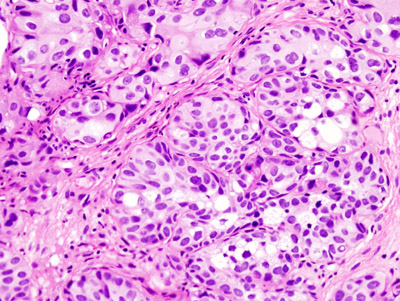

Wilms Tumor

Wilms tumor is a malignant kidney tumor composed of primitive glomeruli, tubules, and stromal cells blastema which is an immature kidney mesenchyme.

The average age of a child who develops a Wilms tumor is 3-years-old.